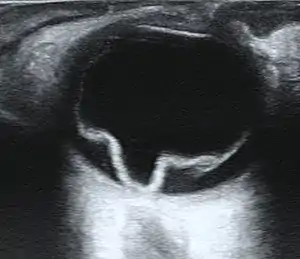

| Ultrasound of a retinal detachment in a patient presenting with complete vision loss and light perception only. | |

Ultrasound, MRI, and CT scan are commonly used to diagnose retinal detachment.